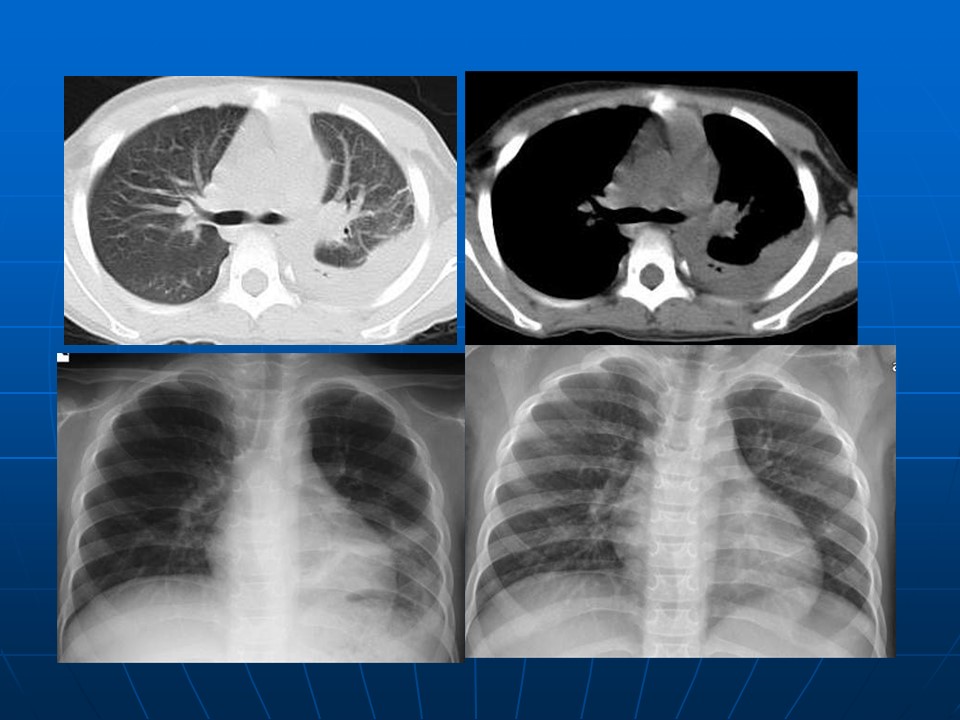

【PPT】早期肺癌易漏诊征象分析